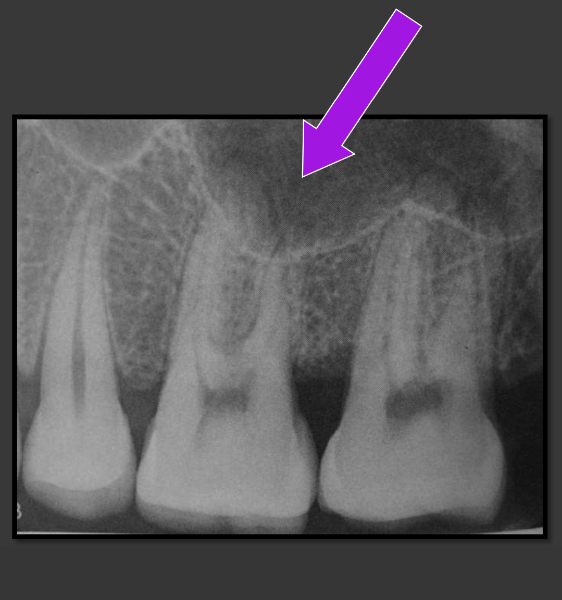

What does the lip line look like in a radiographic image?

-Radiolucent

-Horizontal line that runs across the central incisors usually